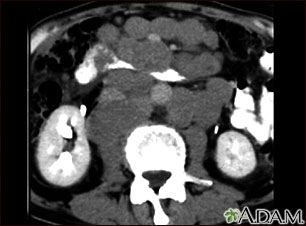

An abdominal CT scan is an imaging test that uses x-rays to create cross-sectional pictures of the belly area. CT stands for computed tomography.

A computer creates separate images of the belly area. These are called slices. These images can be stored, viewed on a monitor, printed on film or saved to a disk. Three-dimensional models of the belly area can be made by stacking the slices together.